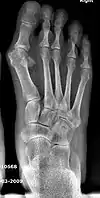

Primus varus deformity is the leaning of the first metatarsal bone away from the second metatarsal and towards the opposite foot (Fig. 1). As it leans over, its head sticks out to form the bunion bump and it also widens the forefoot to cause shoes feeling too tight. Thus when bunion pain becomes unmanageable, surgical correction is to narrow the forefoot by repositioning of the first metatarsal head back to its normal position. This can be done by osteotomy (bone-breaking), soft tissue (non-osteotomy) or fusion techniques.

Syndesmosis procedure addresses specifically the two fundamental problems of metatarsus primus varus deformity that gives rise to the bunion deformity. They are leaning and instability of the first metatarsal bone . Syndesmosis procedure uprights the leaning first metatarsal bone with strong binding sutures between it and the second metatarsal bone (Fig. 2) and then also stabilizes it uniquely by creating a fibrous connecting bridge between these two bones (Fig. 3, 4). First metatarsal bone can be readily realigned because by definition of the metatarsus primus varus deformity its first metatarsal is abnormally loose and mobile.